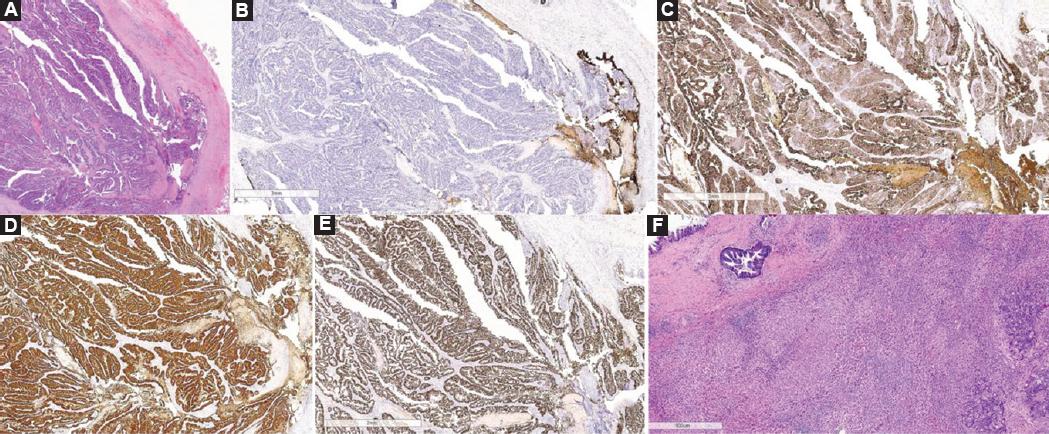

La distinción anatomopatológica entre colangiocarcinoma y metástasis con invasión biliar es difícil si solo se utiliza hematoxilina-eosina, siendo de gran utilidad las técnicas de inmunohistoquímica. La mayoría de las metástasis de cáncer de colon son CK7− y CK20+, mientras que los tumores originados en el epitelio de la vía biliar suelen ser CK7+ y CK20−11. Una expresión CK7−/CK20 + tiene un valor predictivo positivo del 93% para metástasis de cáncer colorrectal14. Por otro lado, la proteína SATB2 es un marcador nuclear del tracto gastrointestinal inferior que aparece en el 85% de los casos de CCR, de modo que la positividad para SATB2 o CK20 diagnostica el 97% de los CCR. El marcador CDX2, aunque no es específico del CCR, pues también se expresa en otras neoplasias, refuerza el diagnóstico (Fig. 3)15.

Figura 3 Estudio inmunohistoquímico. A: tinción de hematoxilina-eosina. Crecimiento endoluminal de adenocarcinoma colónico en la vía biliar, con invasión de la pared. B: negatividad para CK7, con control interno del epitelio conservado de la vía biliar. C: positividad para CK20 en la tumoración. D: intensa positividad para CDX2 en el tumor. E: intensa positividad en el tumor para SATB2. F: tinción de hematoxilina-eosina. Infiltración hepática (derecha) y afectación del conducto biliar (izquierda).